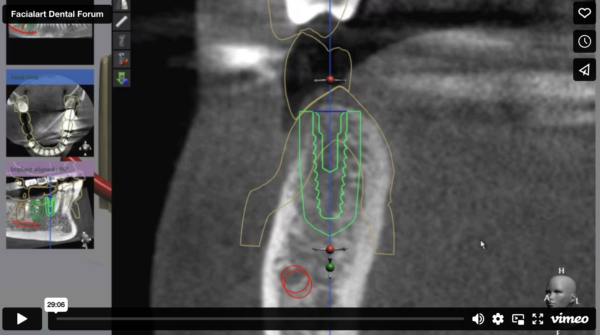

Online Course: Fully-Guided Dental Implants Placement and GBR for Sites #29, 30, 31